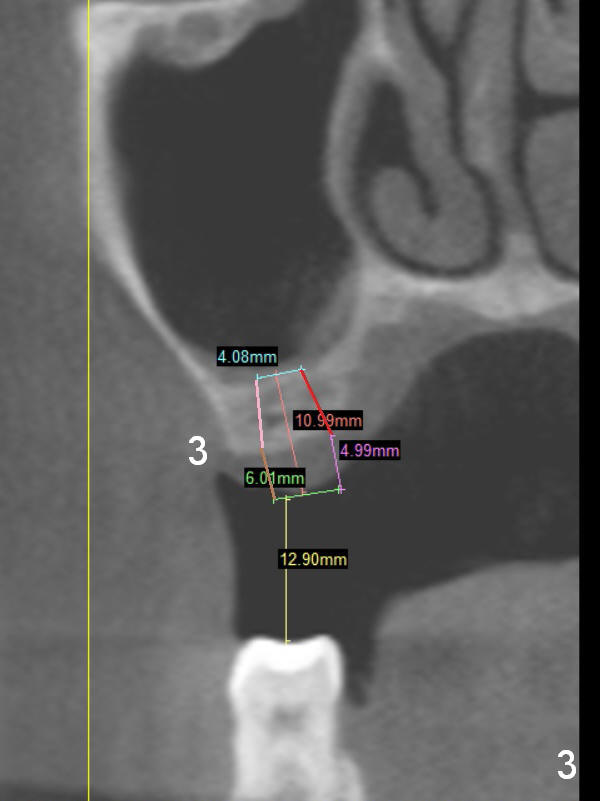

A 68-year-old lady has several missing teeth (Fig.1,2). She has agreed to have an implant at the site of #3 (Fig.3) to stabilize an upper removable partial denture (RPD). The latter will be more stable if an extra implant is placed at #6 (Fig.1,2,6). There is enough bone to place implants at #4,5 (Fig.4,5). Bone density at these sites is low. Osteotomy should be underprep with bone condensation. Edentulous space is high so long abutments are required (9 mm instead of 3 or 5 mm (regularly used)). Angled abutments should be prepared.